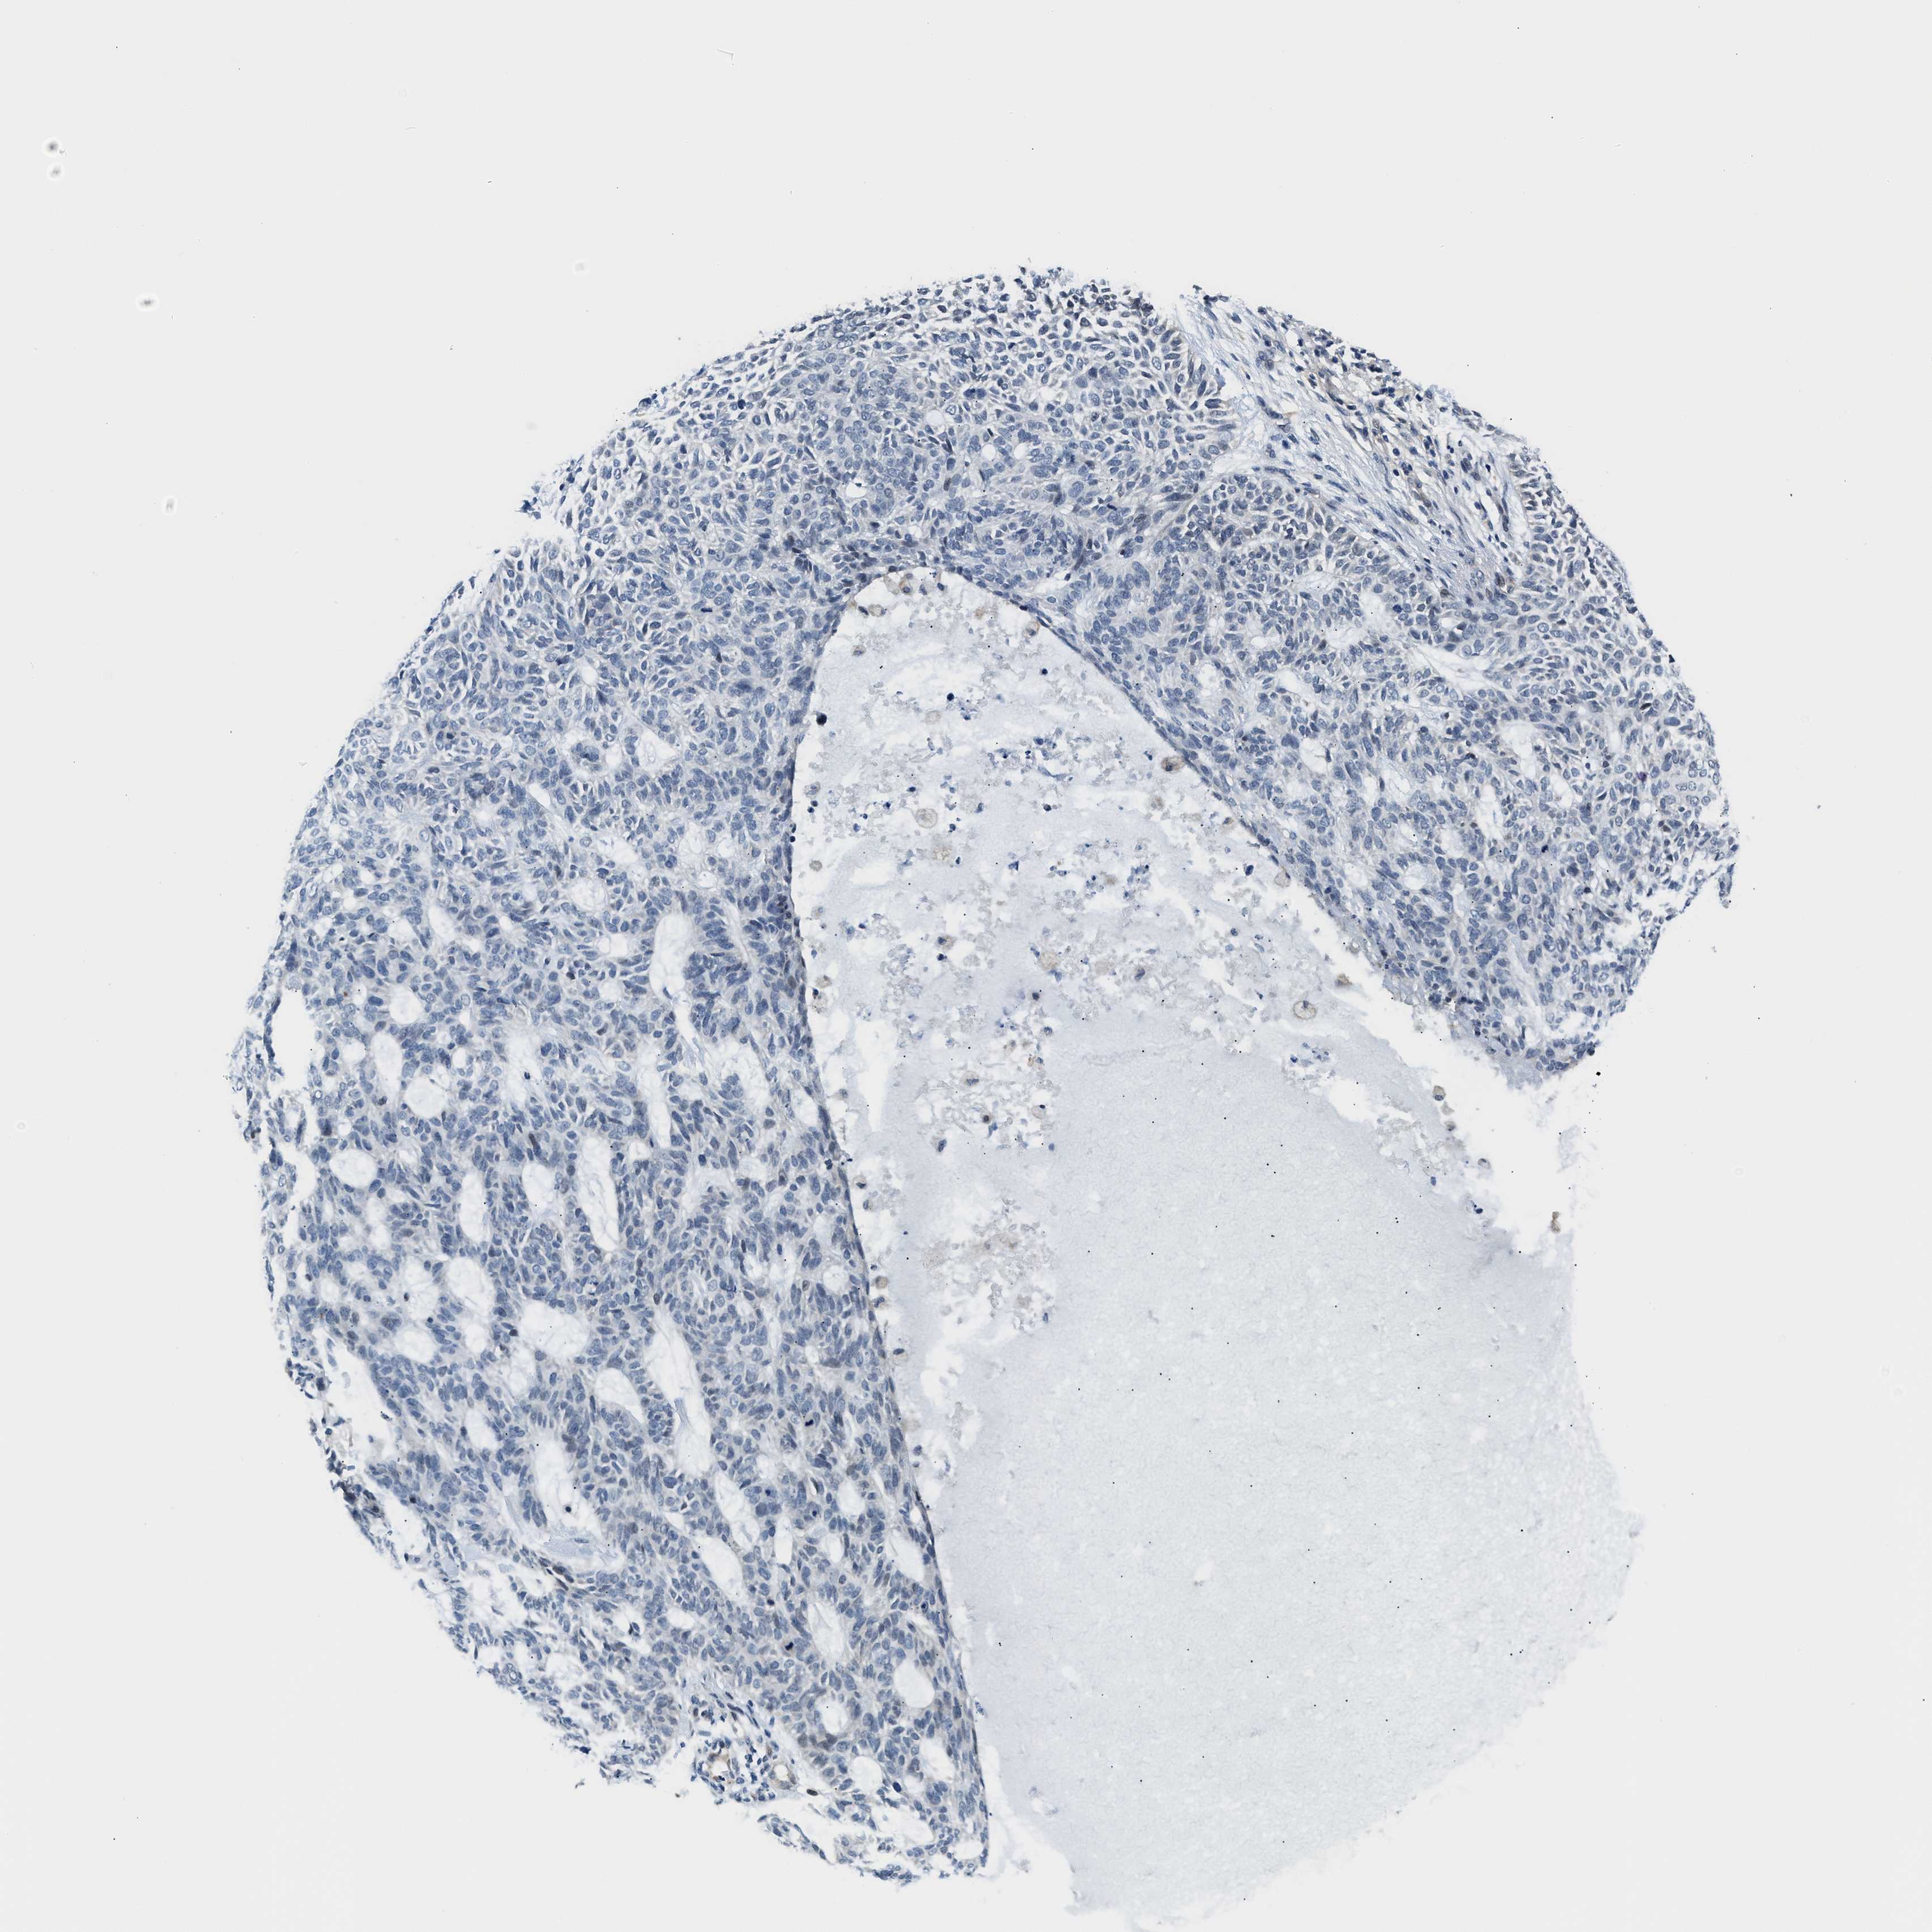

SKIN CANCER - Protein expressioni

A mouse-over function shows sample information and annotation data. Click on an image to view it in a full screen mode. Samples can be filtered based on level of antibody staining by selecting one or several of the following categories: high, medium, low and not detected. The assay and annotation is described here.

Each image is clickable and will lead to virtual microscopy that enables deeper exploration of all samples and also displays staining intensity scores, fraction scores and subcellular localization as well as patient and tissue information for each sample.

Antibody HPA058777

Squamous cell carcinoma, NOS